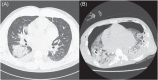

The coronavirus 2019 disease (COVID-19) affected 125 million people worldwide and caused 2.7 million deaths. Some comorbidities are associated with worse prognosis and left ventricular assist device (LVAD) recipients are probably part of this high-risk population. We report a 31-year-old male patient who developed COVID-19 during LVAD implantation. His postoperative period was complicated by severe pneumonia and mechanical ventilation (MV) leading to right ventricular failure (RVF) and inotrope necessity. He experienced multiple complications, but eventually recovered. We present a systematic review of LVAD recipients and COVID-19. Among 14 patients, the mean age was 62.7 years, 78.5% were male. A total of 5 patients (35.7%) required MV and 3 patients (21.4%) died. A total of 2 patients (14.2%) had thromboembolic events. This case and systematic review suggest LVAD recipients are at particular risk of unfavorable outcomes and they may be more susceptible to RVF in the setting of COVID-19, particularly during perioperative period.